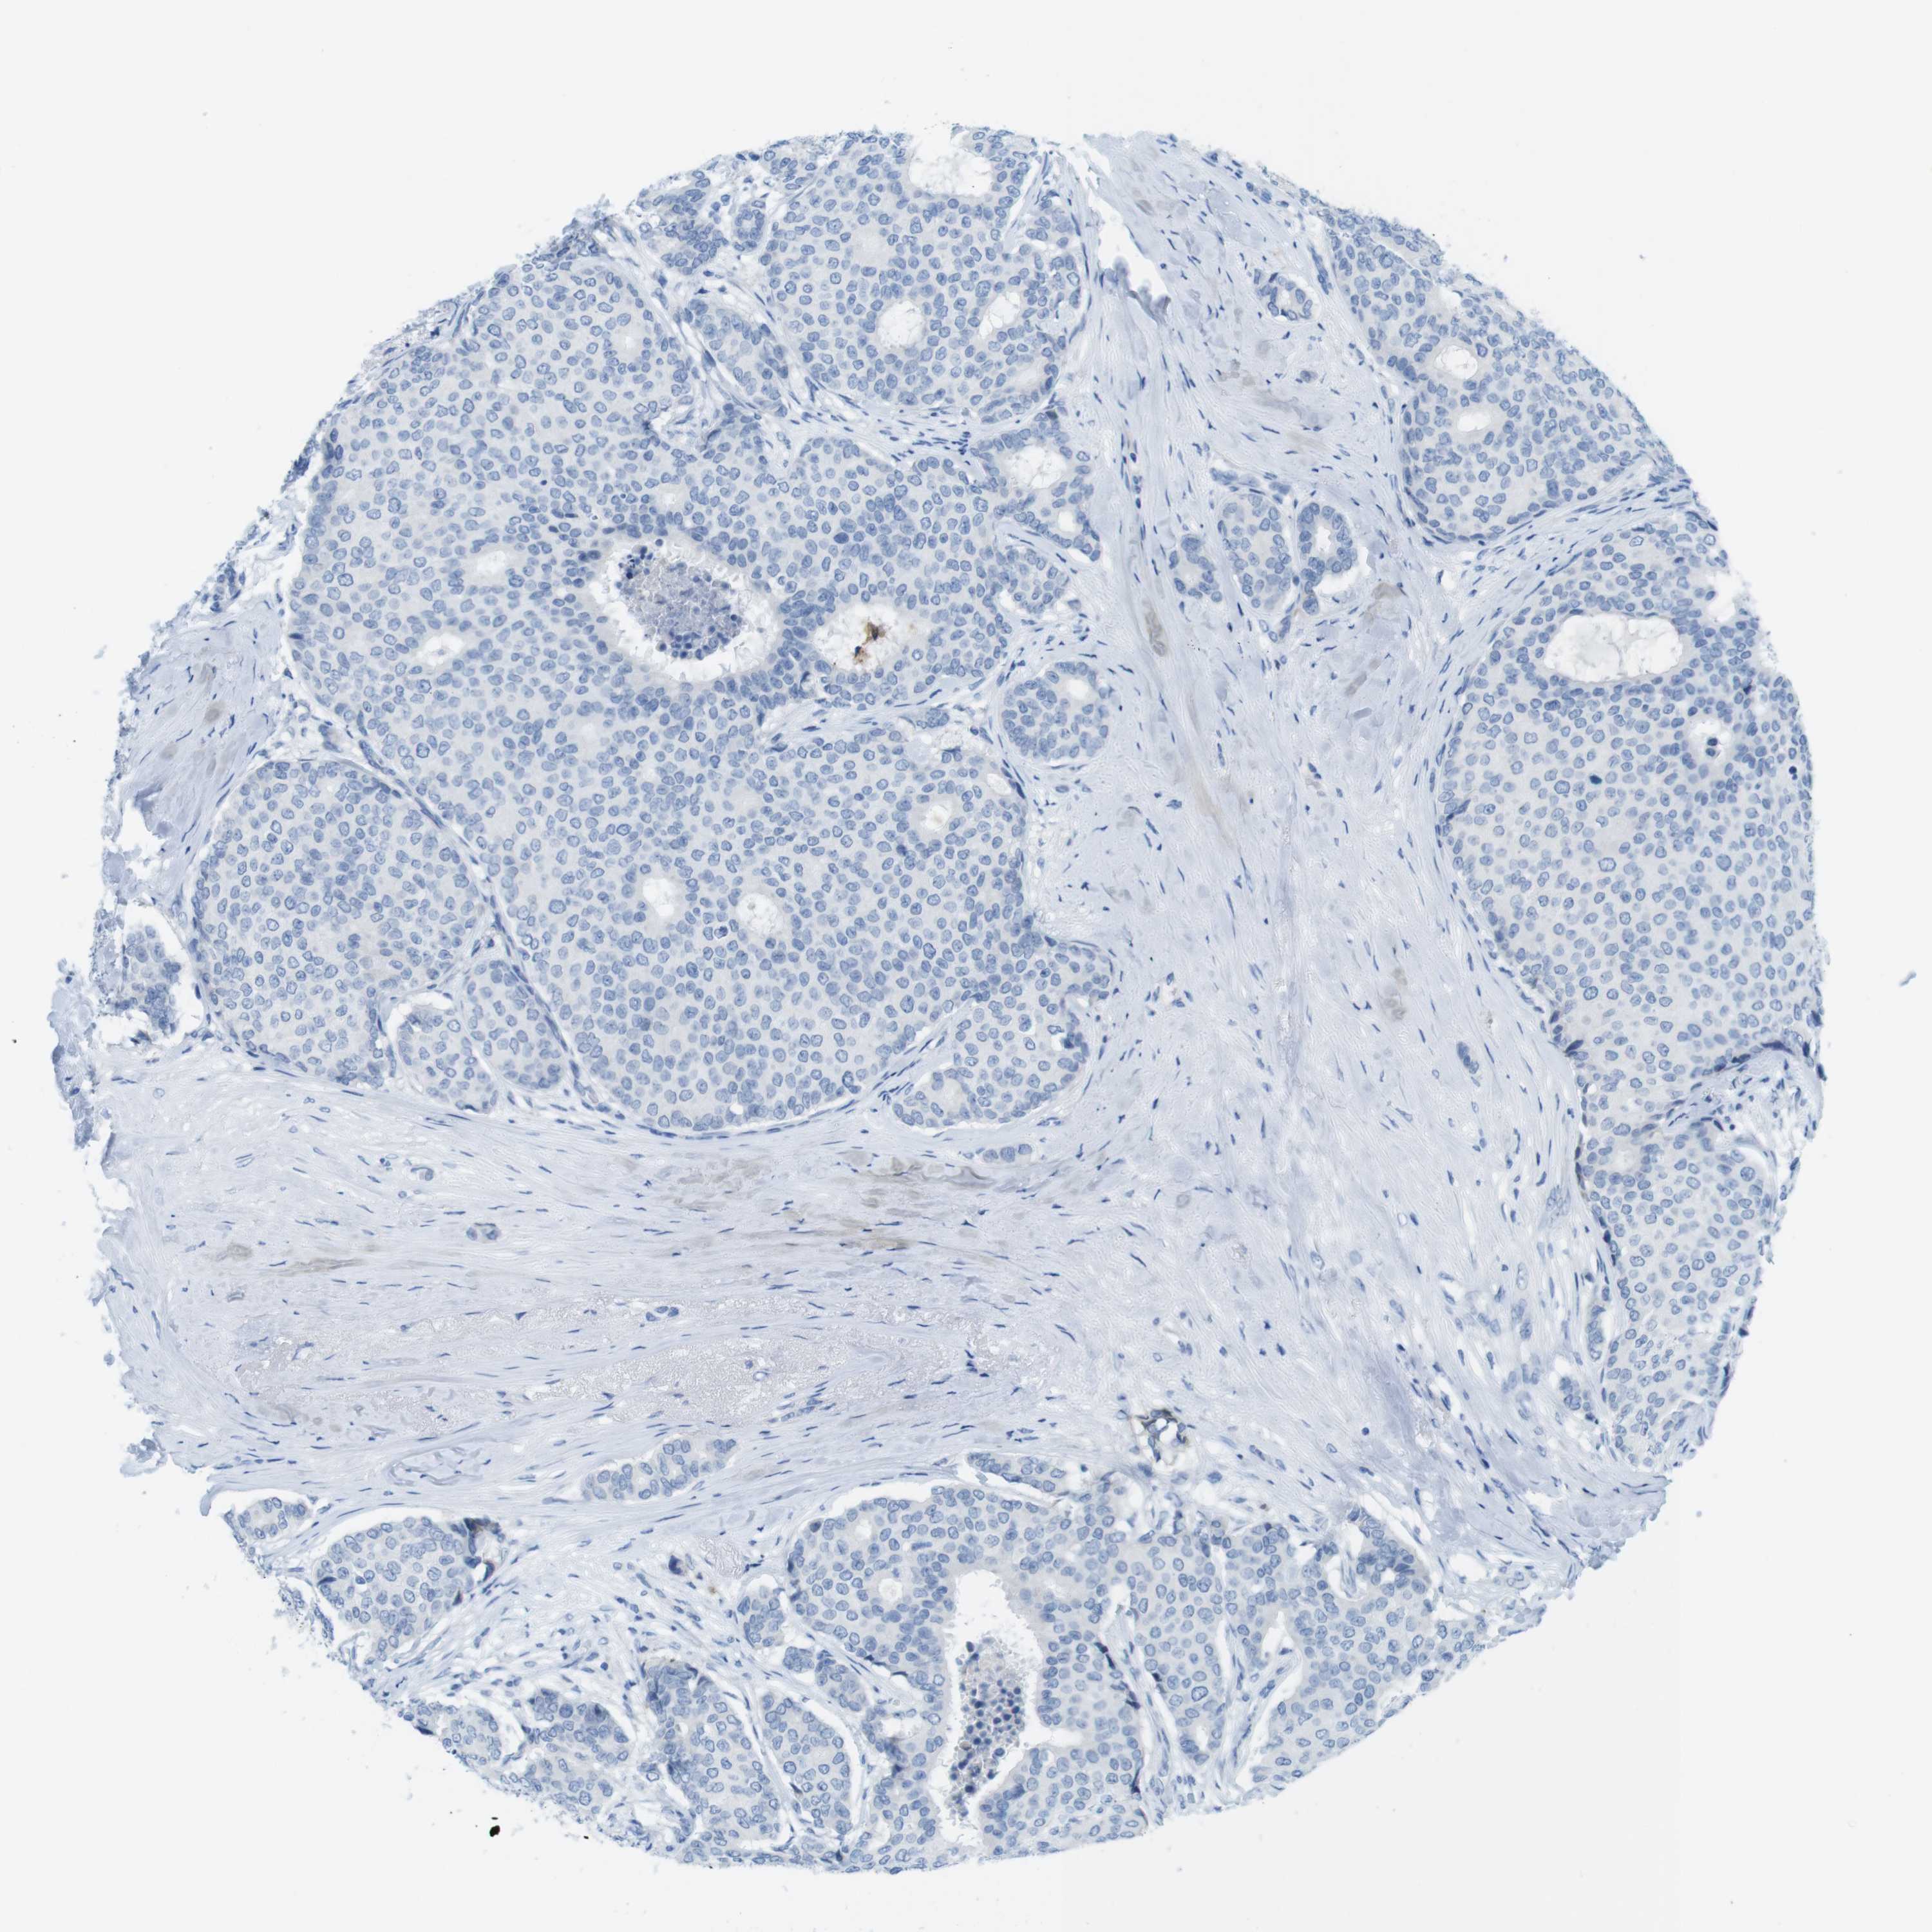

Breast cancer

Human cancer